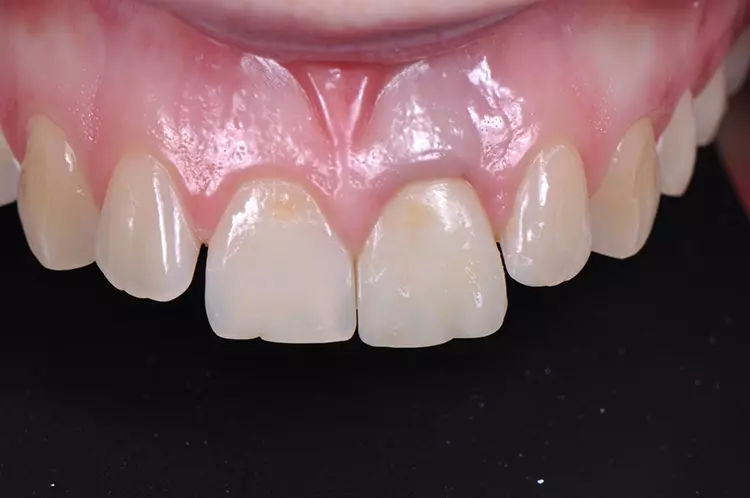

Im Rahmen des Erstgespräches berichtete die junge Patientin von einem Sturzereignis, bei dem der Schneidezahn frakturierte. Ihr damaliger Zahnarzt führte eine Wurzelkanalbehandlung durch und versorgte den Zahn mit einer Krone aus Lithiumdisilikat. Das anfänglich sehr ansprechende ästhetische Behandlungsergebnis hätte sich jedoch nach der Eingliederung mit der Zeit verändert und die Patientin stellte eine zunehmende Verfärbung der Frontzahnkrone fest (Abb. 2 und 3).

Dies kann aus einer nachträglich eingetretenen Verfärbung des devitalen Zahnes resultieren. Durch die sehr hohe Transluzenz der Glasphase einer Lithiumdisilikat-Restauration kann die dunkle Stumpffarbe durchschlagen und zu einem ästhetisch störenden „Grauschleier“ führen. In einem intensiven Beratungs- und Aufklärungsgespräch wurden der Patientin die Schwierigkeiten und Herausforderungen einer Einzelzahnkrone in der ästhetischen Zone bei einer hohen Lachlinie mit Exposition der Gingiva dargestellt.

Trotz der aufgeführten Risiken und Unwägbarkeiten wünschte die junge Patientin eine Neuversorgung des Zahnes, um eine bestmögliche Ästhetik zu erreichen. Gleichzeitig sollten ihre natürliche Zahnfarbe und die individuelle Zahnstellung nicht verändert werden.